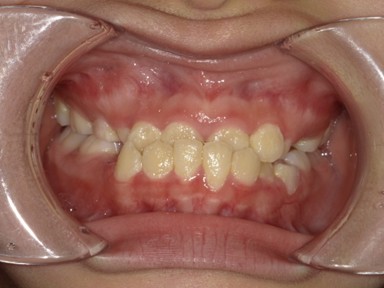

| 主訴 | 生えてきた下の永久歯が曲がっている。これから生えてくる歯も並ぶか心配。 |

| 治療内容 | マイオブレース(J1 → J2 → K3 → T4)と拡大床(BB1)を使用しました。 口腔周囲筋トレーニングも併用しました。 (抜歯:なし、ワイヤー矯正:使用せず) |

| 治療期間 | 78ヶ月(永久歯列完成まで経過観察) ※治療開始から2年間は毎月通院し、その後は3~4か月に1回の頻度で経過観察を継続。 |

| 治療回数 | 38回 |

| 想定されたリスク | 抜歯や全顎ワイヤー矯正のリスクがありました。 |